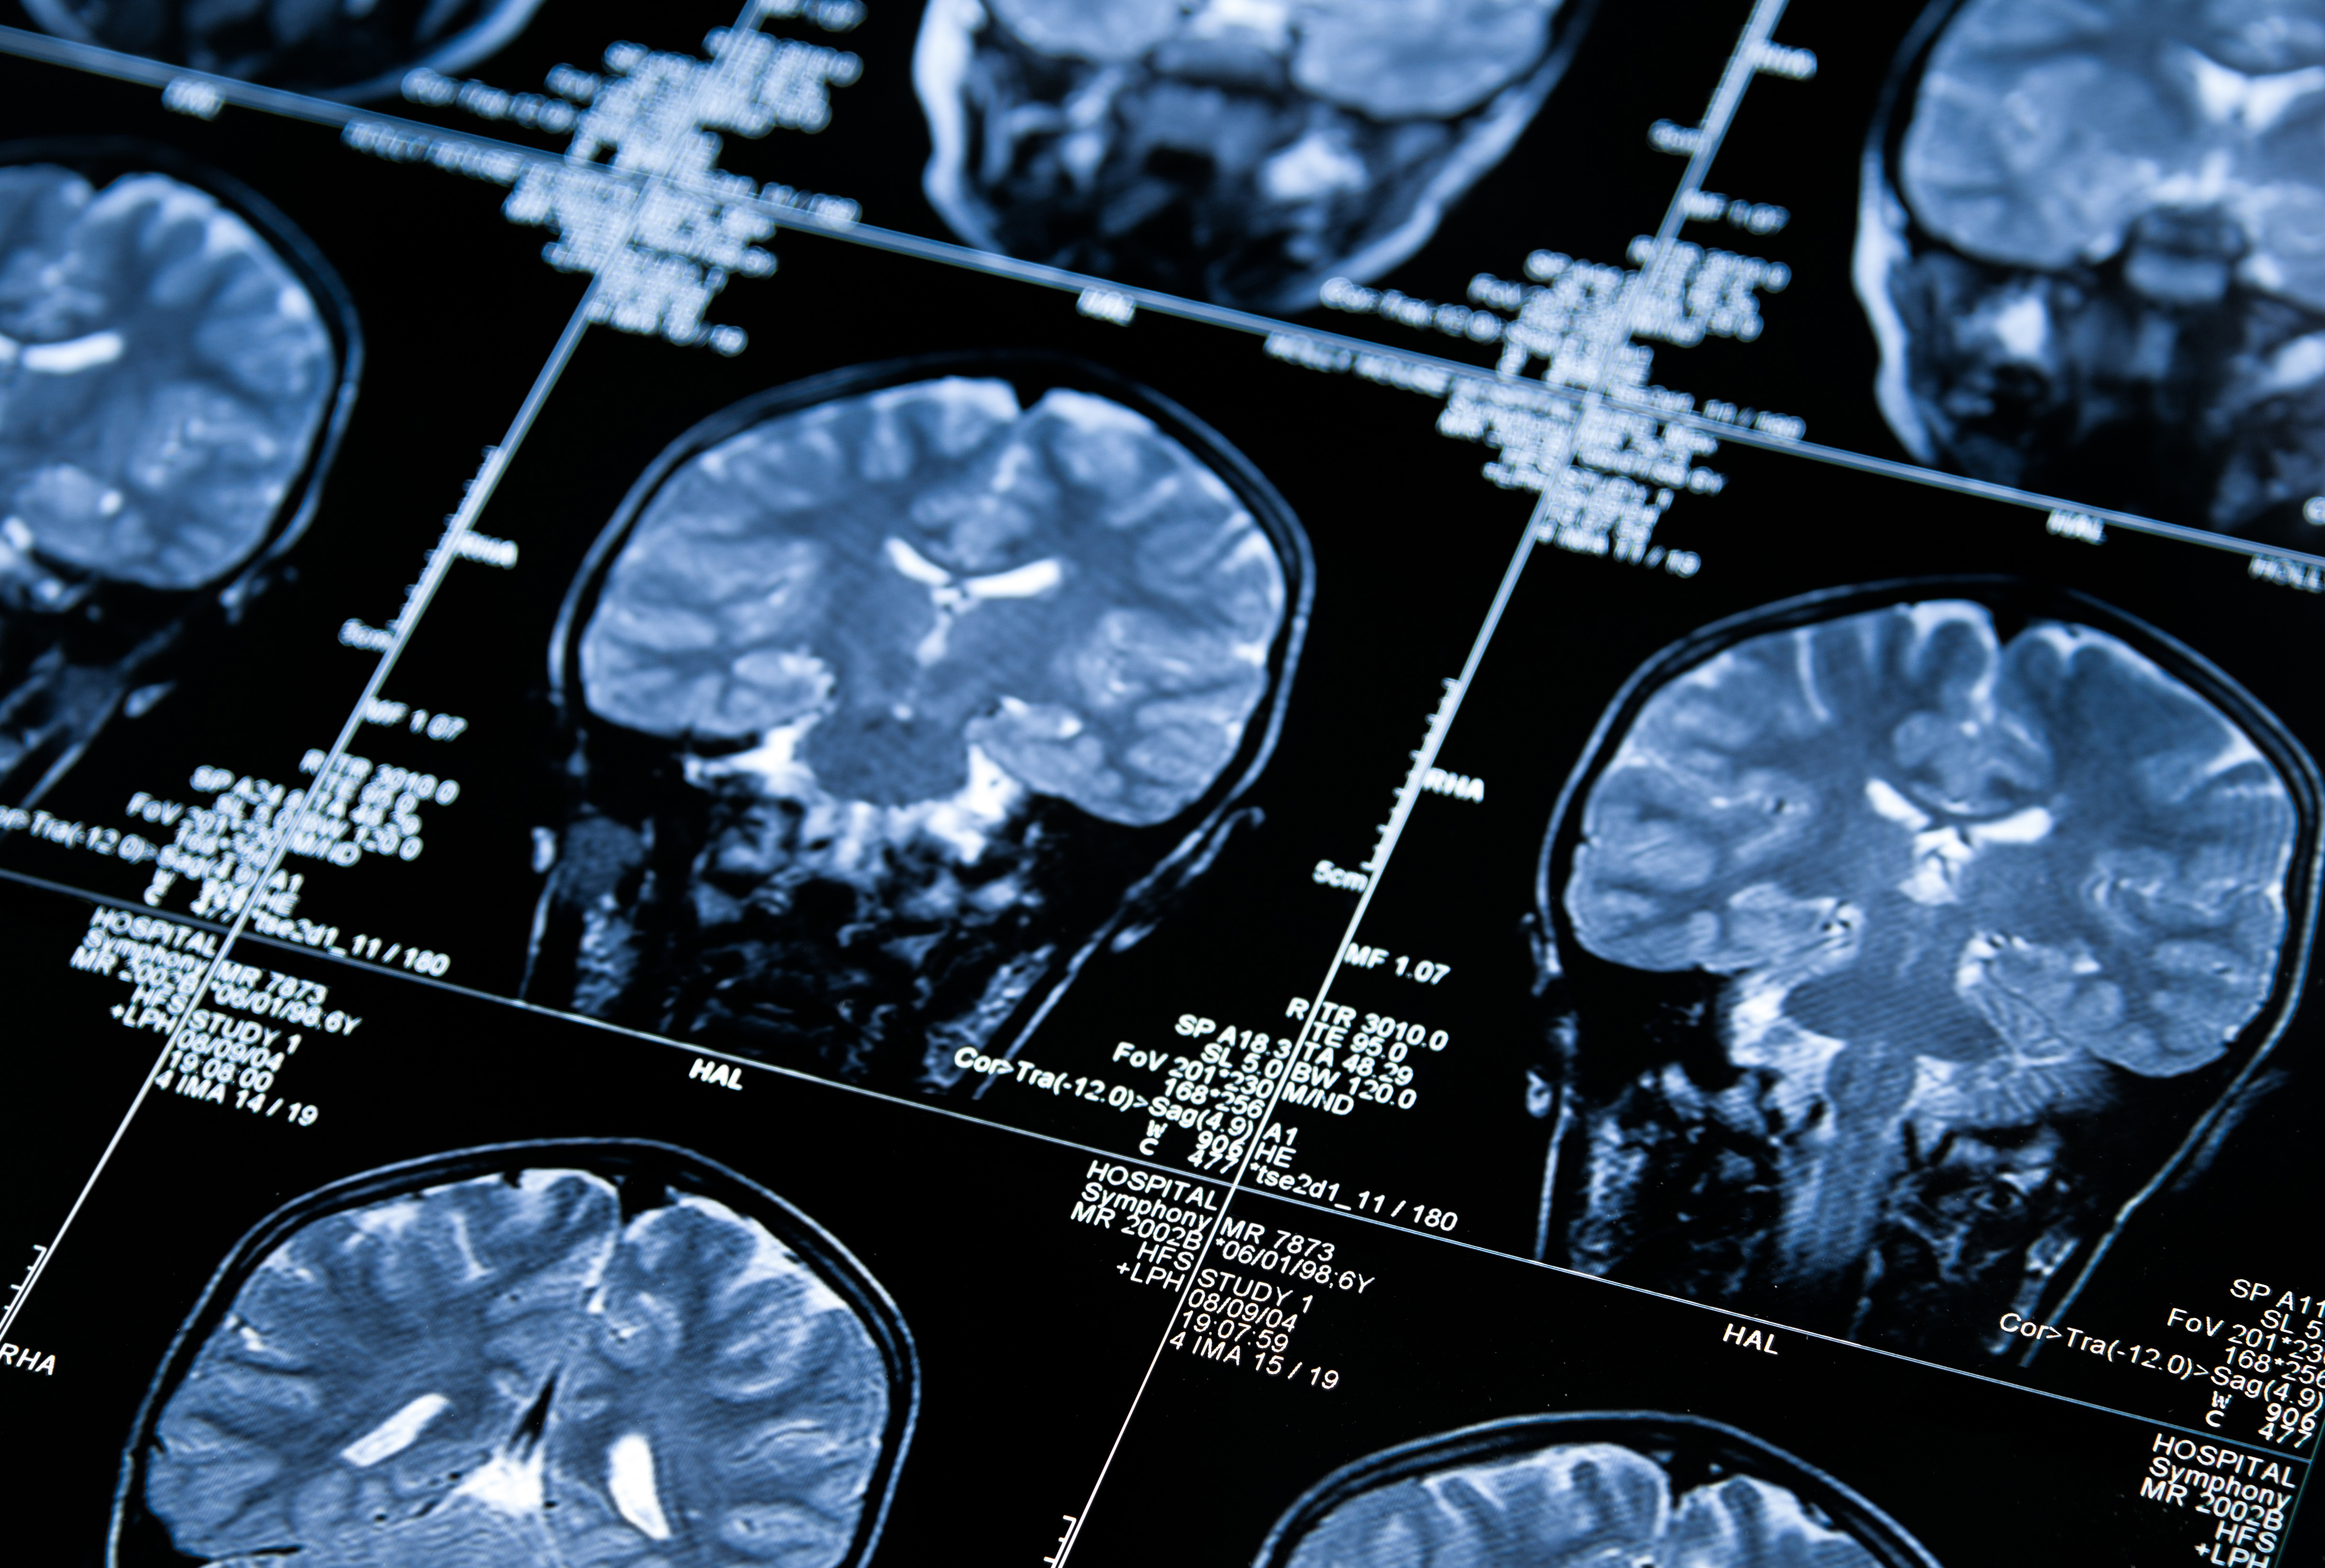

Led by Professor John O'Brien this study involves 300 Prevent Dementia participants undergoing PET-CT scanning to investigate levels of brain amyloid in mid-life.